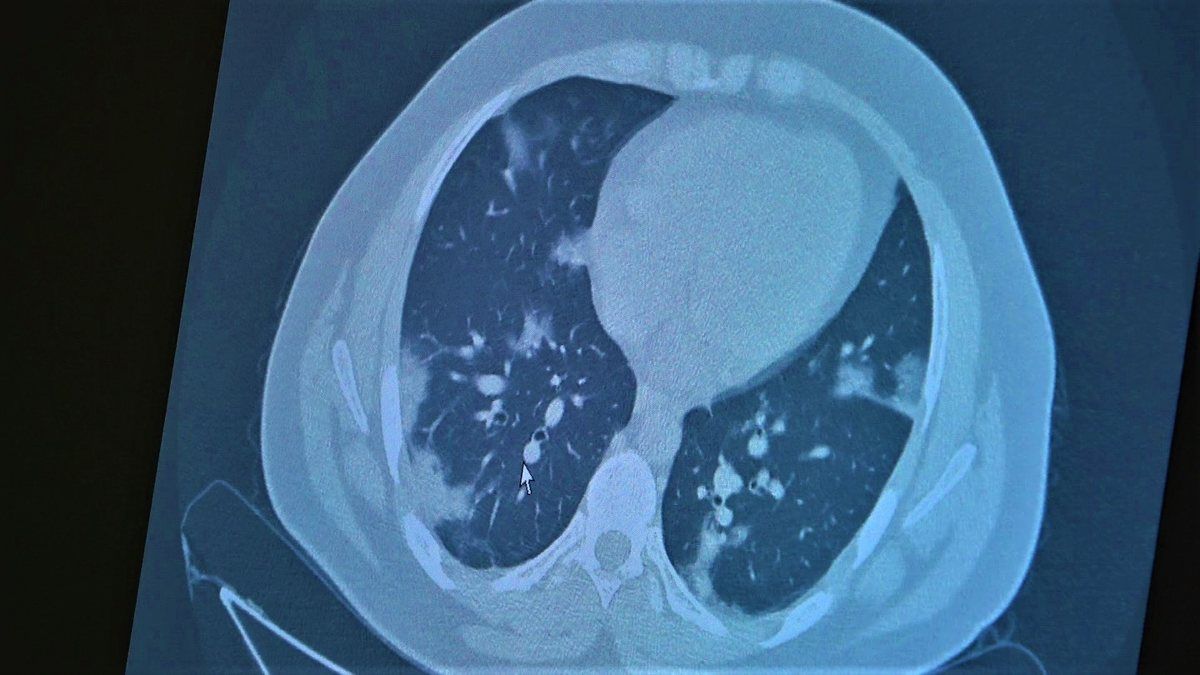

14 yaşında pozitif olan bir diğer çocuğumuz ise aşı randevusu almış ama aşısını olmadan ateş ve öksürükle başvurdu. Halen şanslıyız. Çocuklar çok hızlı tedaviye yanıt veriyor. Düzeldi. Çekilen tomografisinde ise bilaterel yaygın tutulumları vardı. Bu ise 24 yaşında genç hastanın akciğer tomografisi. Bu kişide yaygın akciğer tutulumları görüldü. Bunu da tedavi ettik. Önümüzdeki aylarda ne getirecek ne götürecek beraber göreceğiz. Özellikle havaların soğumasıyla kapalı ortamlarda geçilen zamanın ve kalabalıkların etkisiyle vaka sayılarının önümüzdeki günlerde artacağını biliyoruz. Şu an gerçekten hastalık gençlerde 30 -40 yaş altı gençlerde görülmeye başladı. Poliklinik şartlarında olanların büyük bir kısmı 30 yaş altı hastalar. Servislerde yatanlarda orta yaş ve altı nüfus. Yoğun bakımda yatanların büyük bir kısmı ise aşısız erişkin insanlardan oluşuyor.”